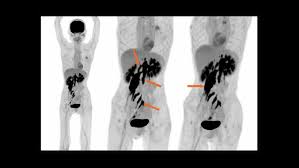

F-Conal FDG PET Scan in Delhi